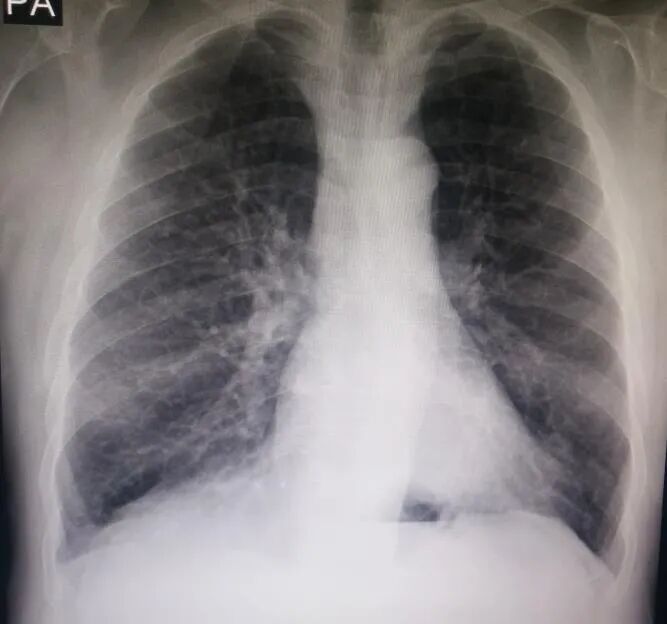

肺动脉栓塞的病例,因其肌酐较高未接受 ct 强化扫描,仅有胸片和胸部

此类病人临床上为常见病人,肺间质病变或者重症肺炎,有的患者在胸片